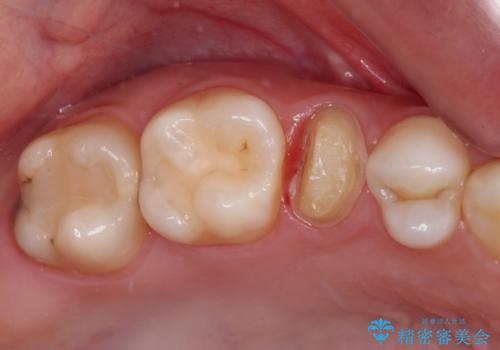

- 根管治療が必要な虫歯を放置した結果、抜歯が必要と診断されたとのことで来院された患者様です。

口腔内の状態やレントゲン写真から判断し、長期的なことを考えると抜歯が無難と思われましたが、それを承知の上で保存するための処置を行うこととしました。

まずは虫歯を除去した上で根管治療を行い、部分矯正により骨内深い位置にまで及んだ健全な部分を引っ張り出すこととしました。

かなり深い位置にまで虫歯が及んでいたため、かなりの量を引っ張り出す必要があり、残された歯根は短く小さい状態となりました。